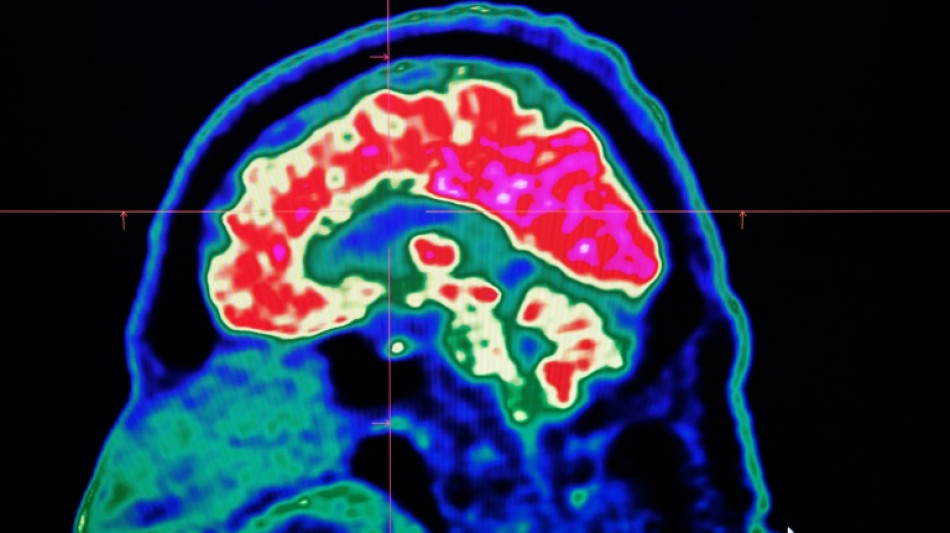

The most prominent study looking at microplastics in brains was published in the journal Nature Medicine in February.

The scientists tested brain tissue from 28 people who died in 2016 and 24 who died last year in the US state of New Mexico, finding that the amount of microplastics in the samples increased over time.

The study made headlines around the world when the lead researcher, US toxicologist Matthew Campen, told the media that they detected the equivalent of a plastic spoon's worth of microplastics in the brains.

Campen also told Nature that he estimated the researchers could isolate around 10 grammes of plastic from a donated human brain -- comparing that amount to an unused crayon.